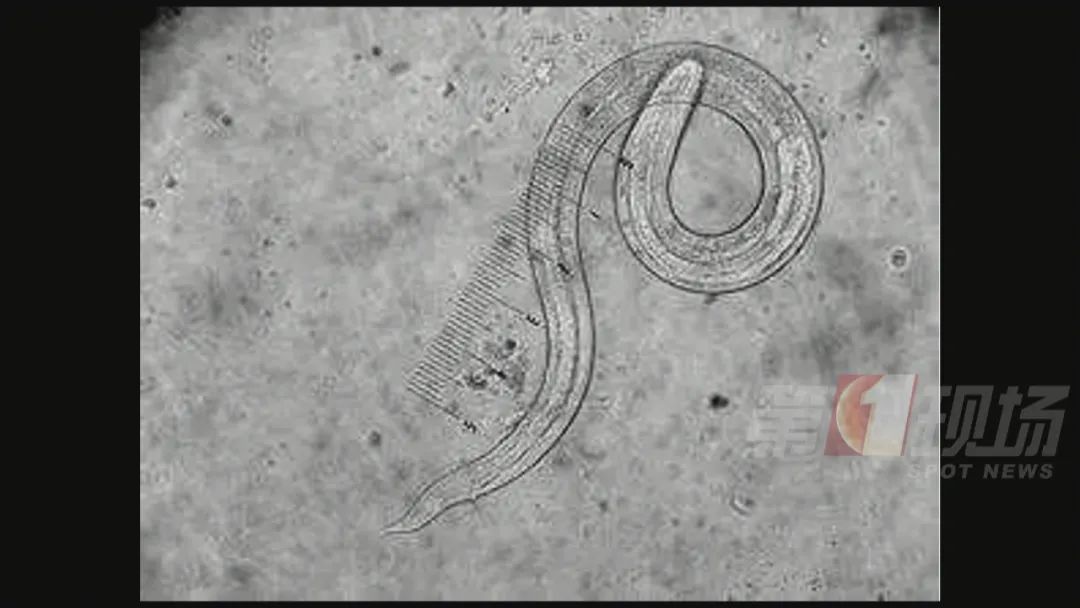

经过两轮检查,在小林的脑脊液里检查出了一种叫“广州管圆线虫”的基因序列,序列数高达上万。

▲广州管源圆寄生虫

广州管圆线虫是1933年由陈心陶首次在广州黑家鼠及褐家鼠体内发现,并命名为广州肺线虫,1946年由Dougherty最后命名为广州管圆线虫。

这种寄生虫主要侵犯人体中枢神经系统,表现为嗜酸粒细胞增多性脑膜炎或脑膜脑炎、脊髓炎等,也可损害肺、眼和鼻,严重者可使人致死或致残。